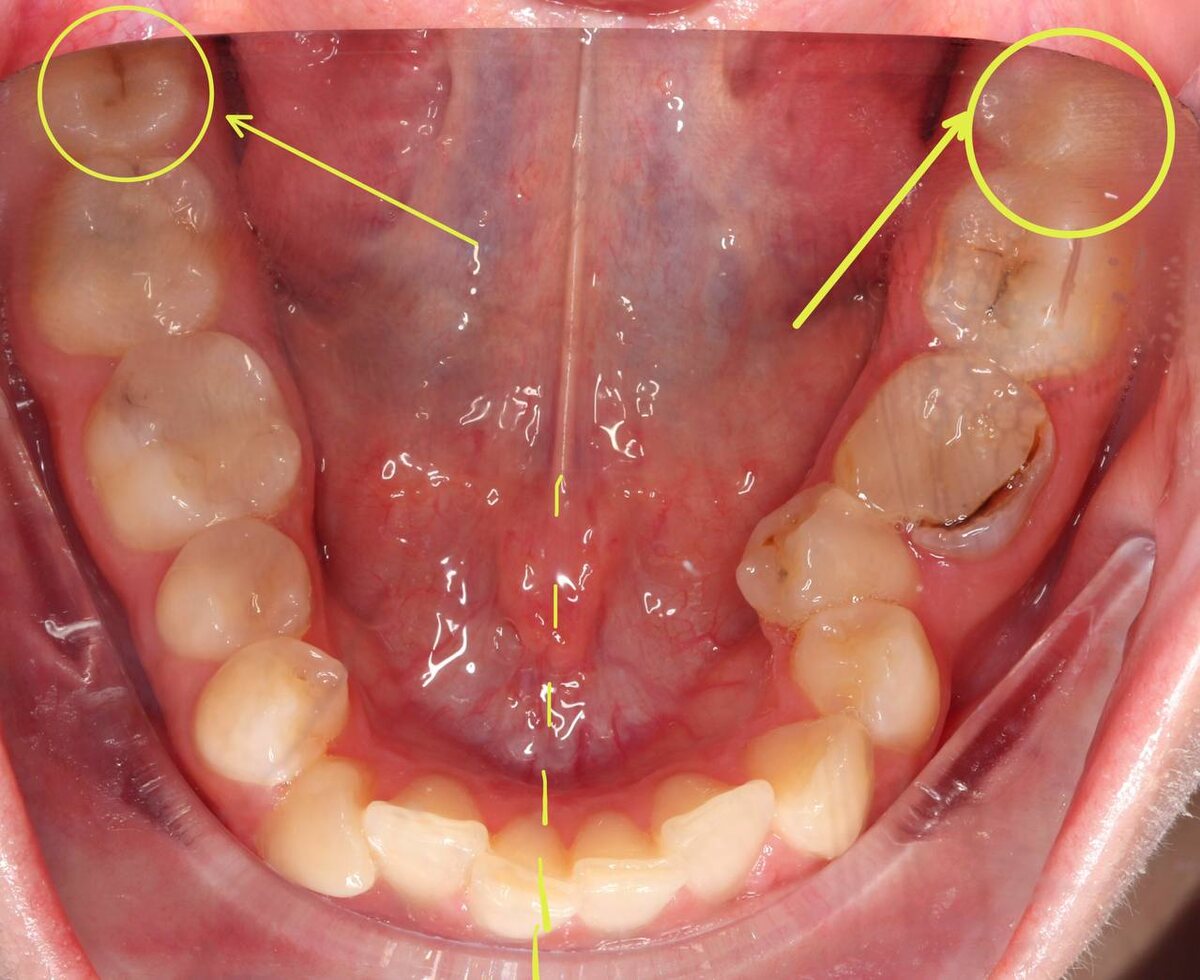

Вот вам первый вопрос:

В этом случае нужно удалять 8ки?